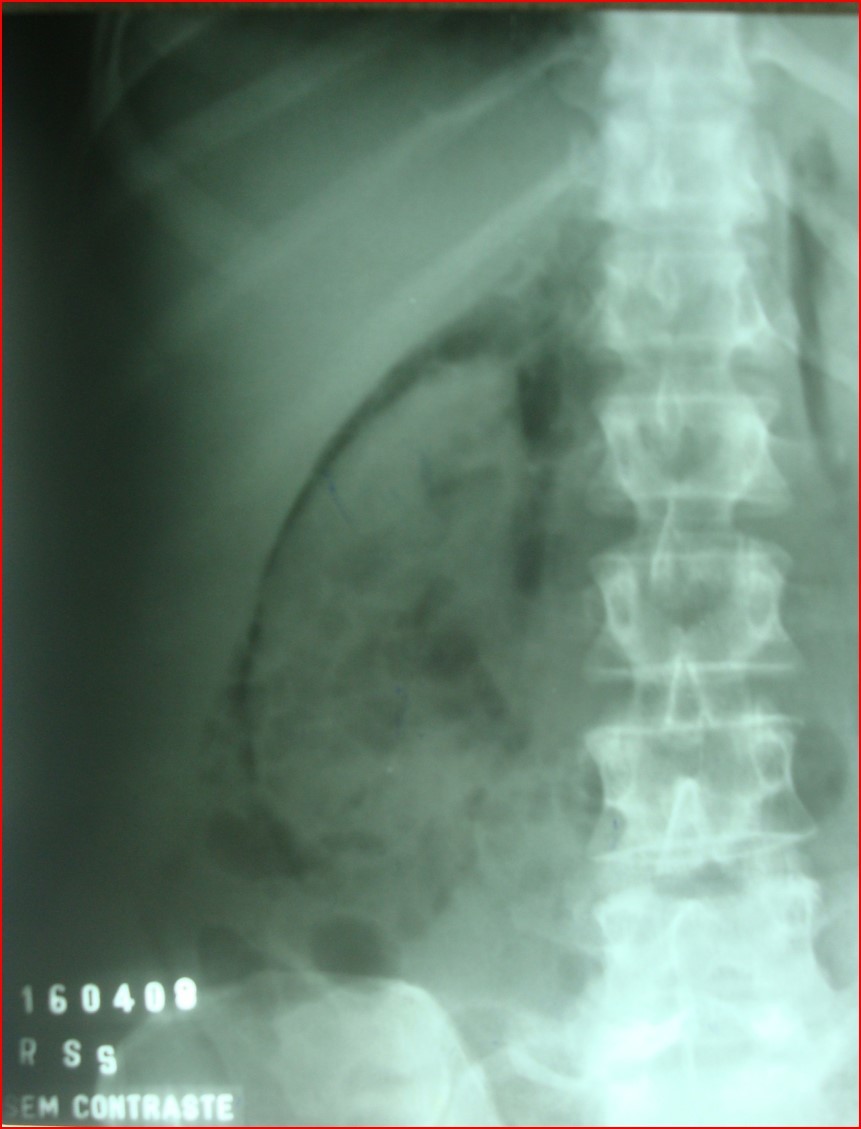

RETROPNEUMOPERITÔNIO

IMAGEM GASOSA ( ESCURA ) CIRCUNDANDO O RIM DIREITO, DECORRENTE DE RUPTURA DUODENAL

ESTE AR, APESAR DE CIRCUNDAR O RIM, SE LOCALIZA NO ESPAÇO PARARRENAL ANTERIOR, A NÃO SER QUE TENHA TAMBÉM ROMPIDO A FÁSCIA RENAL ANTERIOR.